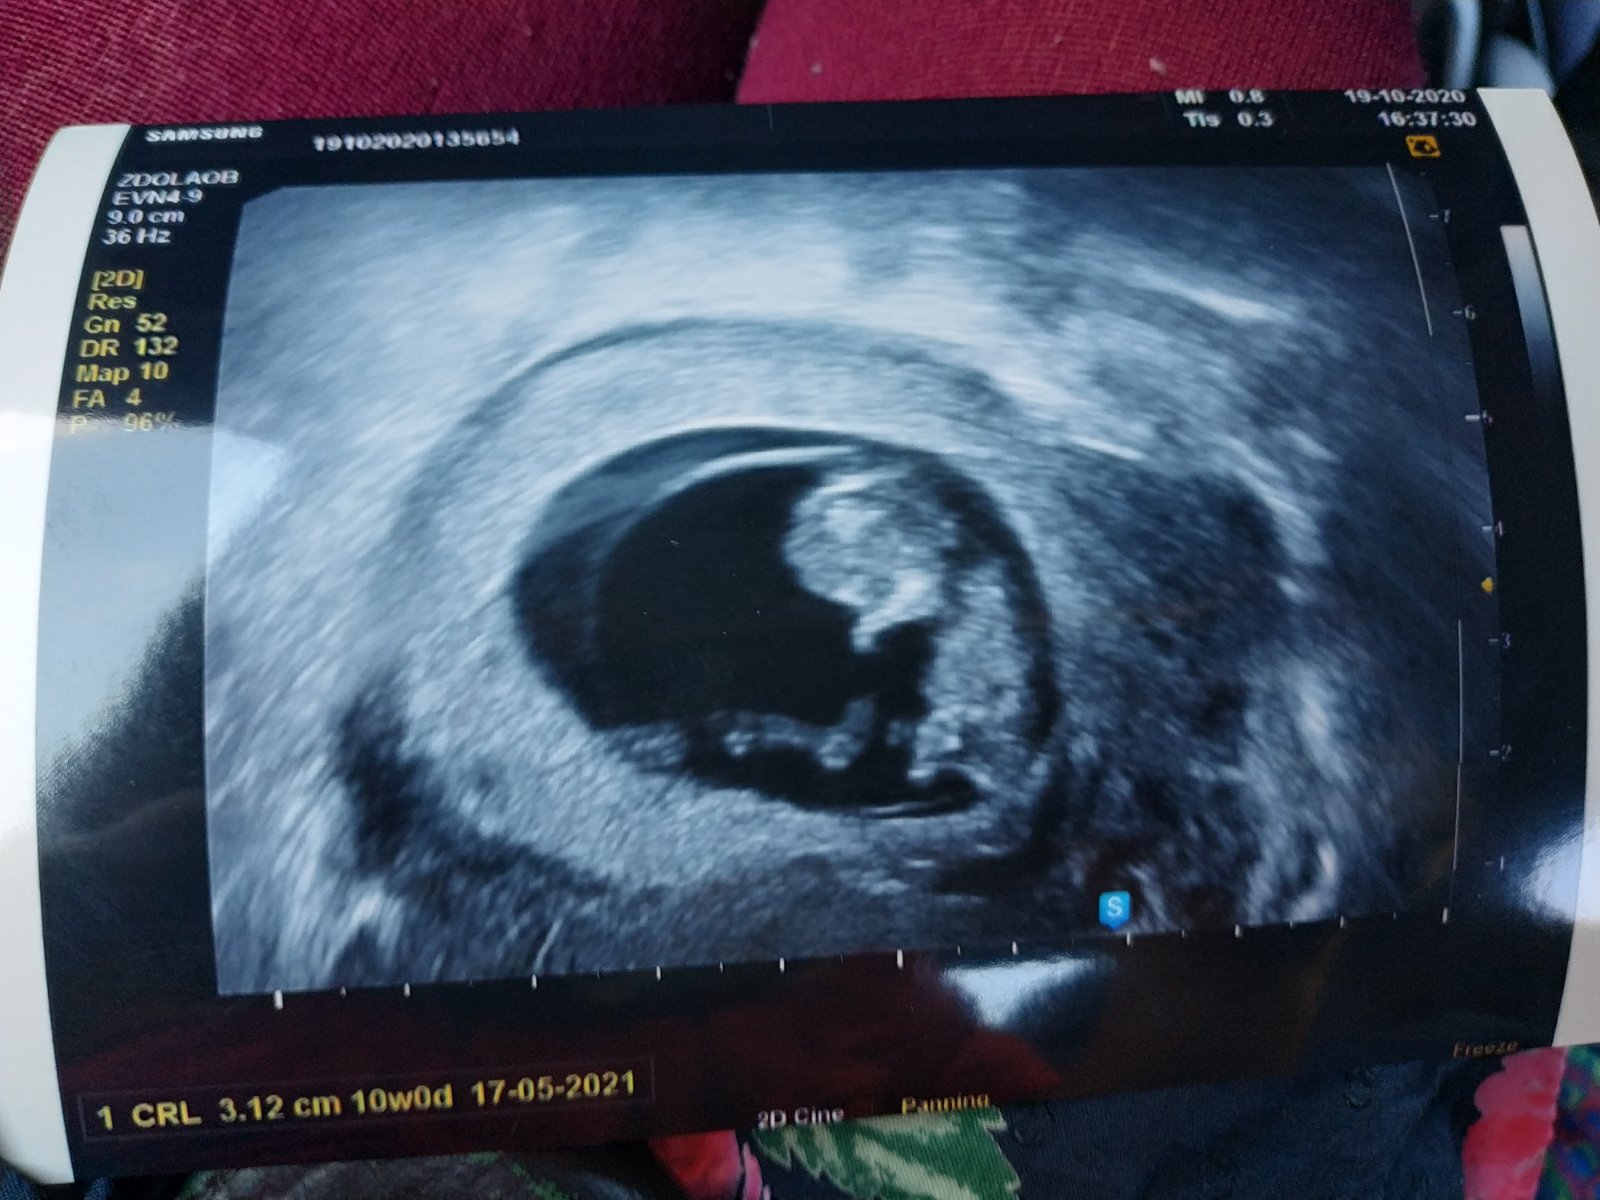

Trochu větší bublinka 😁